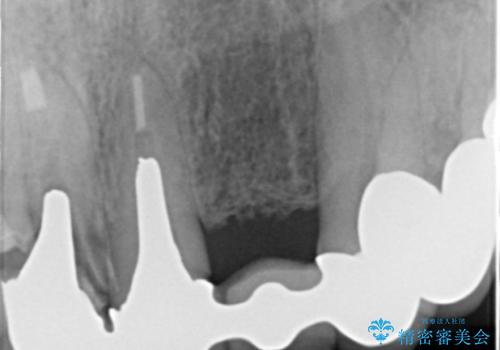

- 若い時に作った前歯のブリッジがの根元が黒くなってきているとのことで来院。

支える歯が1本虫歯がひどく、割れていました。

根の治療からやり直して新しいブリッジにしています。

ブリッジの支台歯は、根の再治療を含めて行なっています。